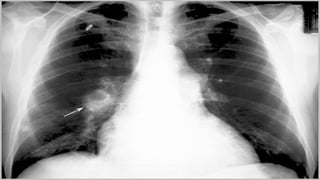

• Radiografia de Tórax;

Avaliação e achadosdiagnósticos • História clínica, sinais e sintomas; • Radiografia de Tórax; • ECG; • Oximetria de pulso; • Gasometria arterial; • Angiografia Pulmonar; • Tomografia helicoidal de tórax; • Ensaio do dímero D (exame de sangue à procura de evidências de coágulos sanguíneos); • Arteriografia.